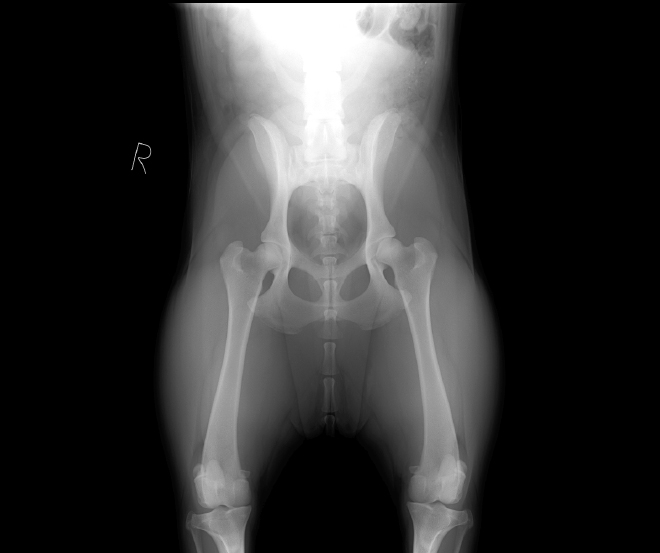

画像検査

レントゲン検査で股関節の状態を確認します。撮影は仰向けで左右対称になるよう固定する「股関節伸展位標準撮影法」で行われるのが一般的な方法ですが、この方法では関節炎などの病変を伴わない状態で股関節の緩みを正確に判断することが難しく、また2歳以上にならないと最終診断が難しいという難点があります。そこで当院では、病変が現れる前から〝股関節の緩み〟を評価できる特殊なレントゲン検査・Penn HIP(ペンヒップ)法を導入、16週齢という幼齢期から科学的に股関節形成不全の予兆を評価し、より正確に早期診断することによって早期の治療につなげることを可能にしています。

Penn HIP

米国ペンシルバニア大学のゲイル・スミス博士によって開発された〝股関節の緩み〟を評価する特殊なレントゲン検査。股関節形成不全を発症するリスクについて科学的に診断することで予防・早期発見・軽症化が可能になります。撮影はPenn HIP認定獣医師のライセンスをもつ獣医師のみが行うことができ、撮影したX線画像を専門機関であるAIS(ANTECH Imaging Services)に送り、評価を依頼します。

[撮影方法]

伸延ストレスをかける専用器具(ディストラクター)を用い、股関節を外側に最大まで伸展させて撮影します。筋肉が弛緩してリラックスした状態で撮影する必要があるため、鎮静剤または全身麻酔を使用します。

Hip-Extended View最初に足を伸展させる一般的な方法で撮影します。股関節の一般状態や骨関節炎の存在を確認するために撮影します。 -

Compression View大腿骨頭が寛骨臼にどれくらいしっかりとはまるか、正中に向かって足を押し込み撮影します。また、股関節の緩みを測定するために必要な大腿骨頭のランドマークを確認します。 -

Distraction View最後に、専用器具を用い、股関節をテコの原理で外すような適度な力を加え、どれくらい股関節が緩むかを確認します。